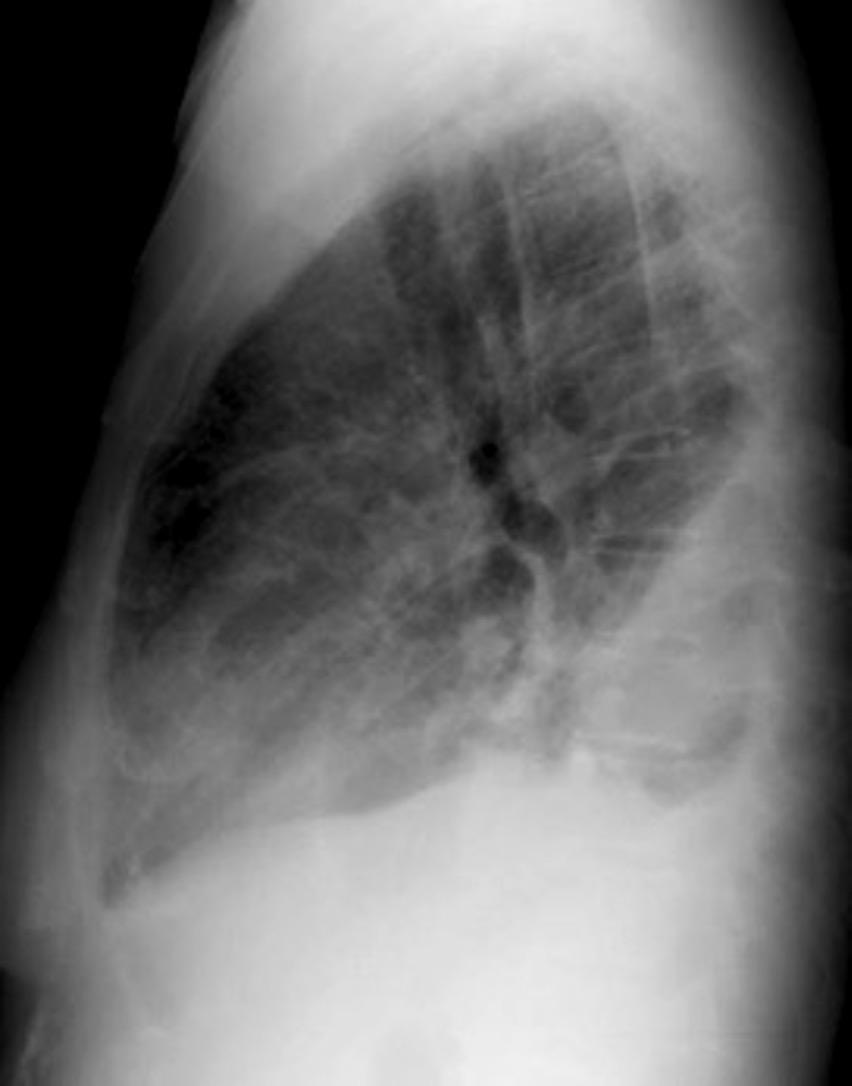

Los hallazgos radiológicos dependen de.

1. Cantidad de líquido

2. Su distribución. (dependiente de la posición)

3. Si es libre o está tabicado (formación de fibrina)

Líquido libre Líquido “subpulmonar”

175 cc

Dec. supino

Líquido en cisura horizontal y accesoria derecha